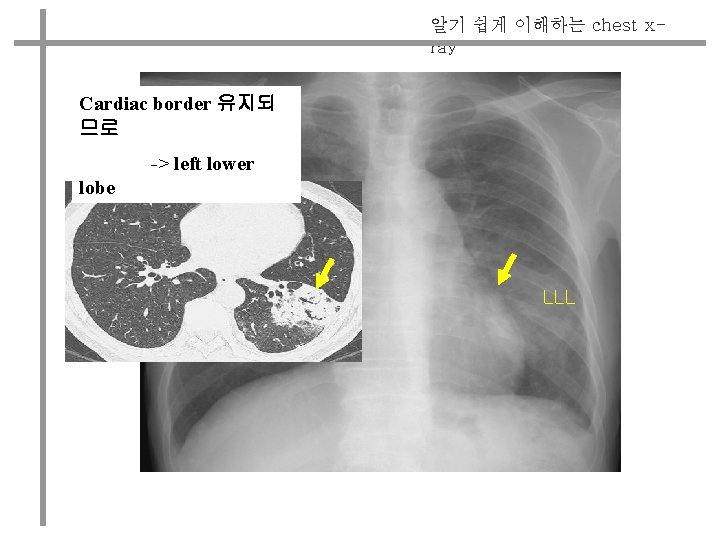

chest xray Cardiac border left lower lobe LLL

알기 쉽게 이해하는 chest xray Cardiac border 유지되 므로 -> left lower lobe LLL